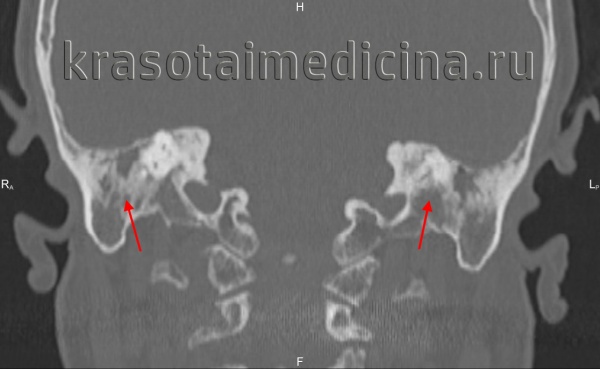

КТ височных костей. С обеих сторон диффузное снижение пневматизации ячеек сосцевидного отростка и пирамиды височной кости за счет отосклероза

Тимпанальный и кохлеарный отосклероз: А. и Б. Аксиальная. В. и Г. Коронарная КТ; Д. Аксиальная МРТ в режиме Т1 после контрастирования.

Подножная пластинка правого стремени утолщена (А и В, стрелки). Грубые спогиозные изменения проникают через костную капсулу (Б и Г, стрелки).